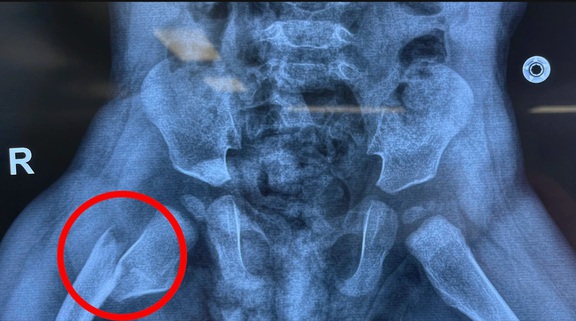

Ngày 19.3, thạc sĩ - bác sĩ chuyên khoa 1 Nguyễn Xuân Trường (Trung tâm Chấn thương chỉnh hình, Bệnh viện đa khoa Tâm Anh TP.HCM) cho biết, kết quả chụp X-quang xác định bé bị gãy xương đùi phải với hai đầu xương gãy bị di lệch. Để đảm bảo quá trình phục hồi tốt nhất, các bác sĩ quyết định áp dụng phương pháp bó bột toàn thân, từ cổ chân đến ngực.

Kết quả chụp X-quang cho thấy vùng đùi phải của bệnh nhi bị gãy xương

ẢNH: T.A